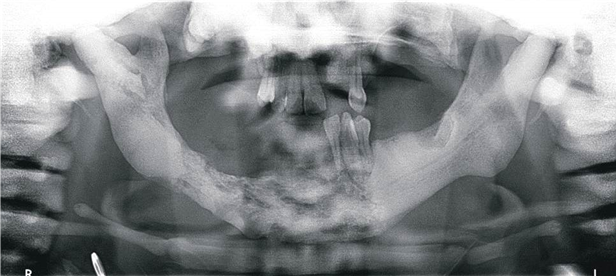

Imagenologicamente, mediante técnica de ortopantomografía, presentaba piezas 32, 33 y 34 con focos apicales. A nivel óseo presentaba en la región anterior mandibular que se extiende a cuerpo mandibular lado derecho desde distal de pieza 34 hasta región molar del lado derecho, una imagen con contornos irregulares, moderada reabsorción ósea y rarefacción ósea con zonas osteolíticas, de bordes poco definidos, mostrando cambio gradual en el patrón de trabeculado y destrucción ósea comprometiendo reborde alveolar y basal mandibular. Hueso trabecular con aumento de densidad ósea y zonas de radiotransparencias mal definidas (figura 1).

Figura 1. Ortopantomografía inicial.